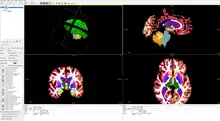

- FreeView, a tool to visualize FreeSurfer output, which can also display common MRI image formats[12]